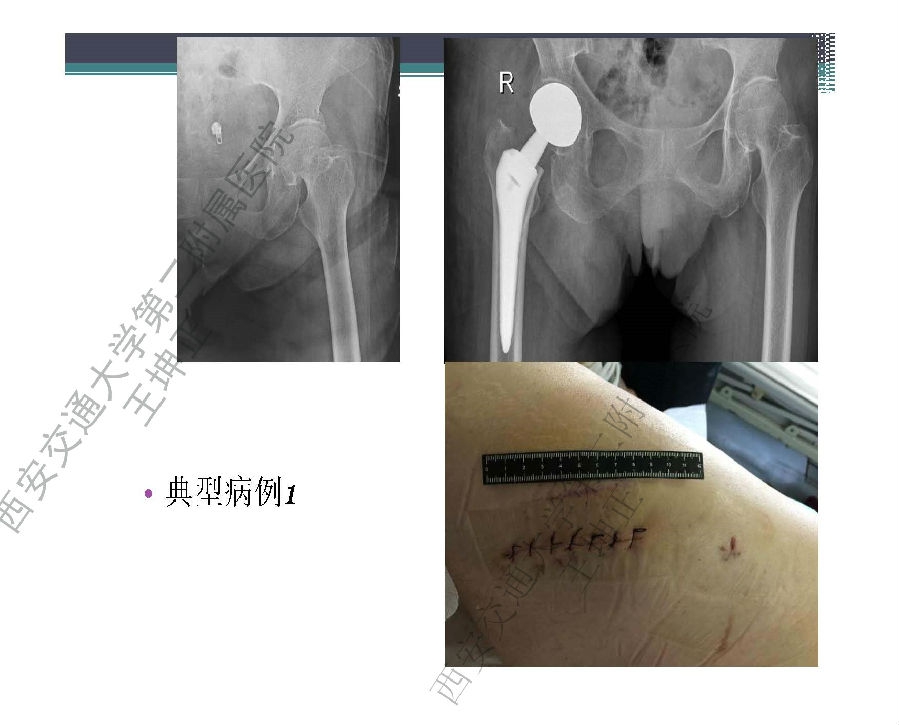

对于关节外科而言快速康复实际上是以病人加速舒适康复为目的,加强围术期的综合管理,包括疼痛和睡眠管理、血栓预防管理、感染预防管理、围术期血液管理,减少放置引流管、尿管、减少止血带应用,减少术后恶心呕吐,尽早进食,尽早康复等,逐步达到无血、无痛、无栓、无感、无肿、无管、无吐、无带等优良效果。为此,小编特邀王坤正教授等多位关节外科的专家参与撰写快速康复外科在关节外科的应用的主题文章,共话“人工关节置换快速康复”新理念,探讨建立符合我国特色的关节置换围手术期管理与快速康复体系,促进我国关节外科技术整体发展与提高。